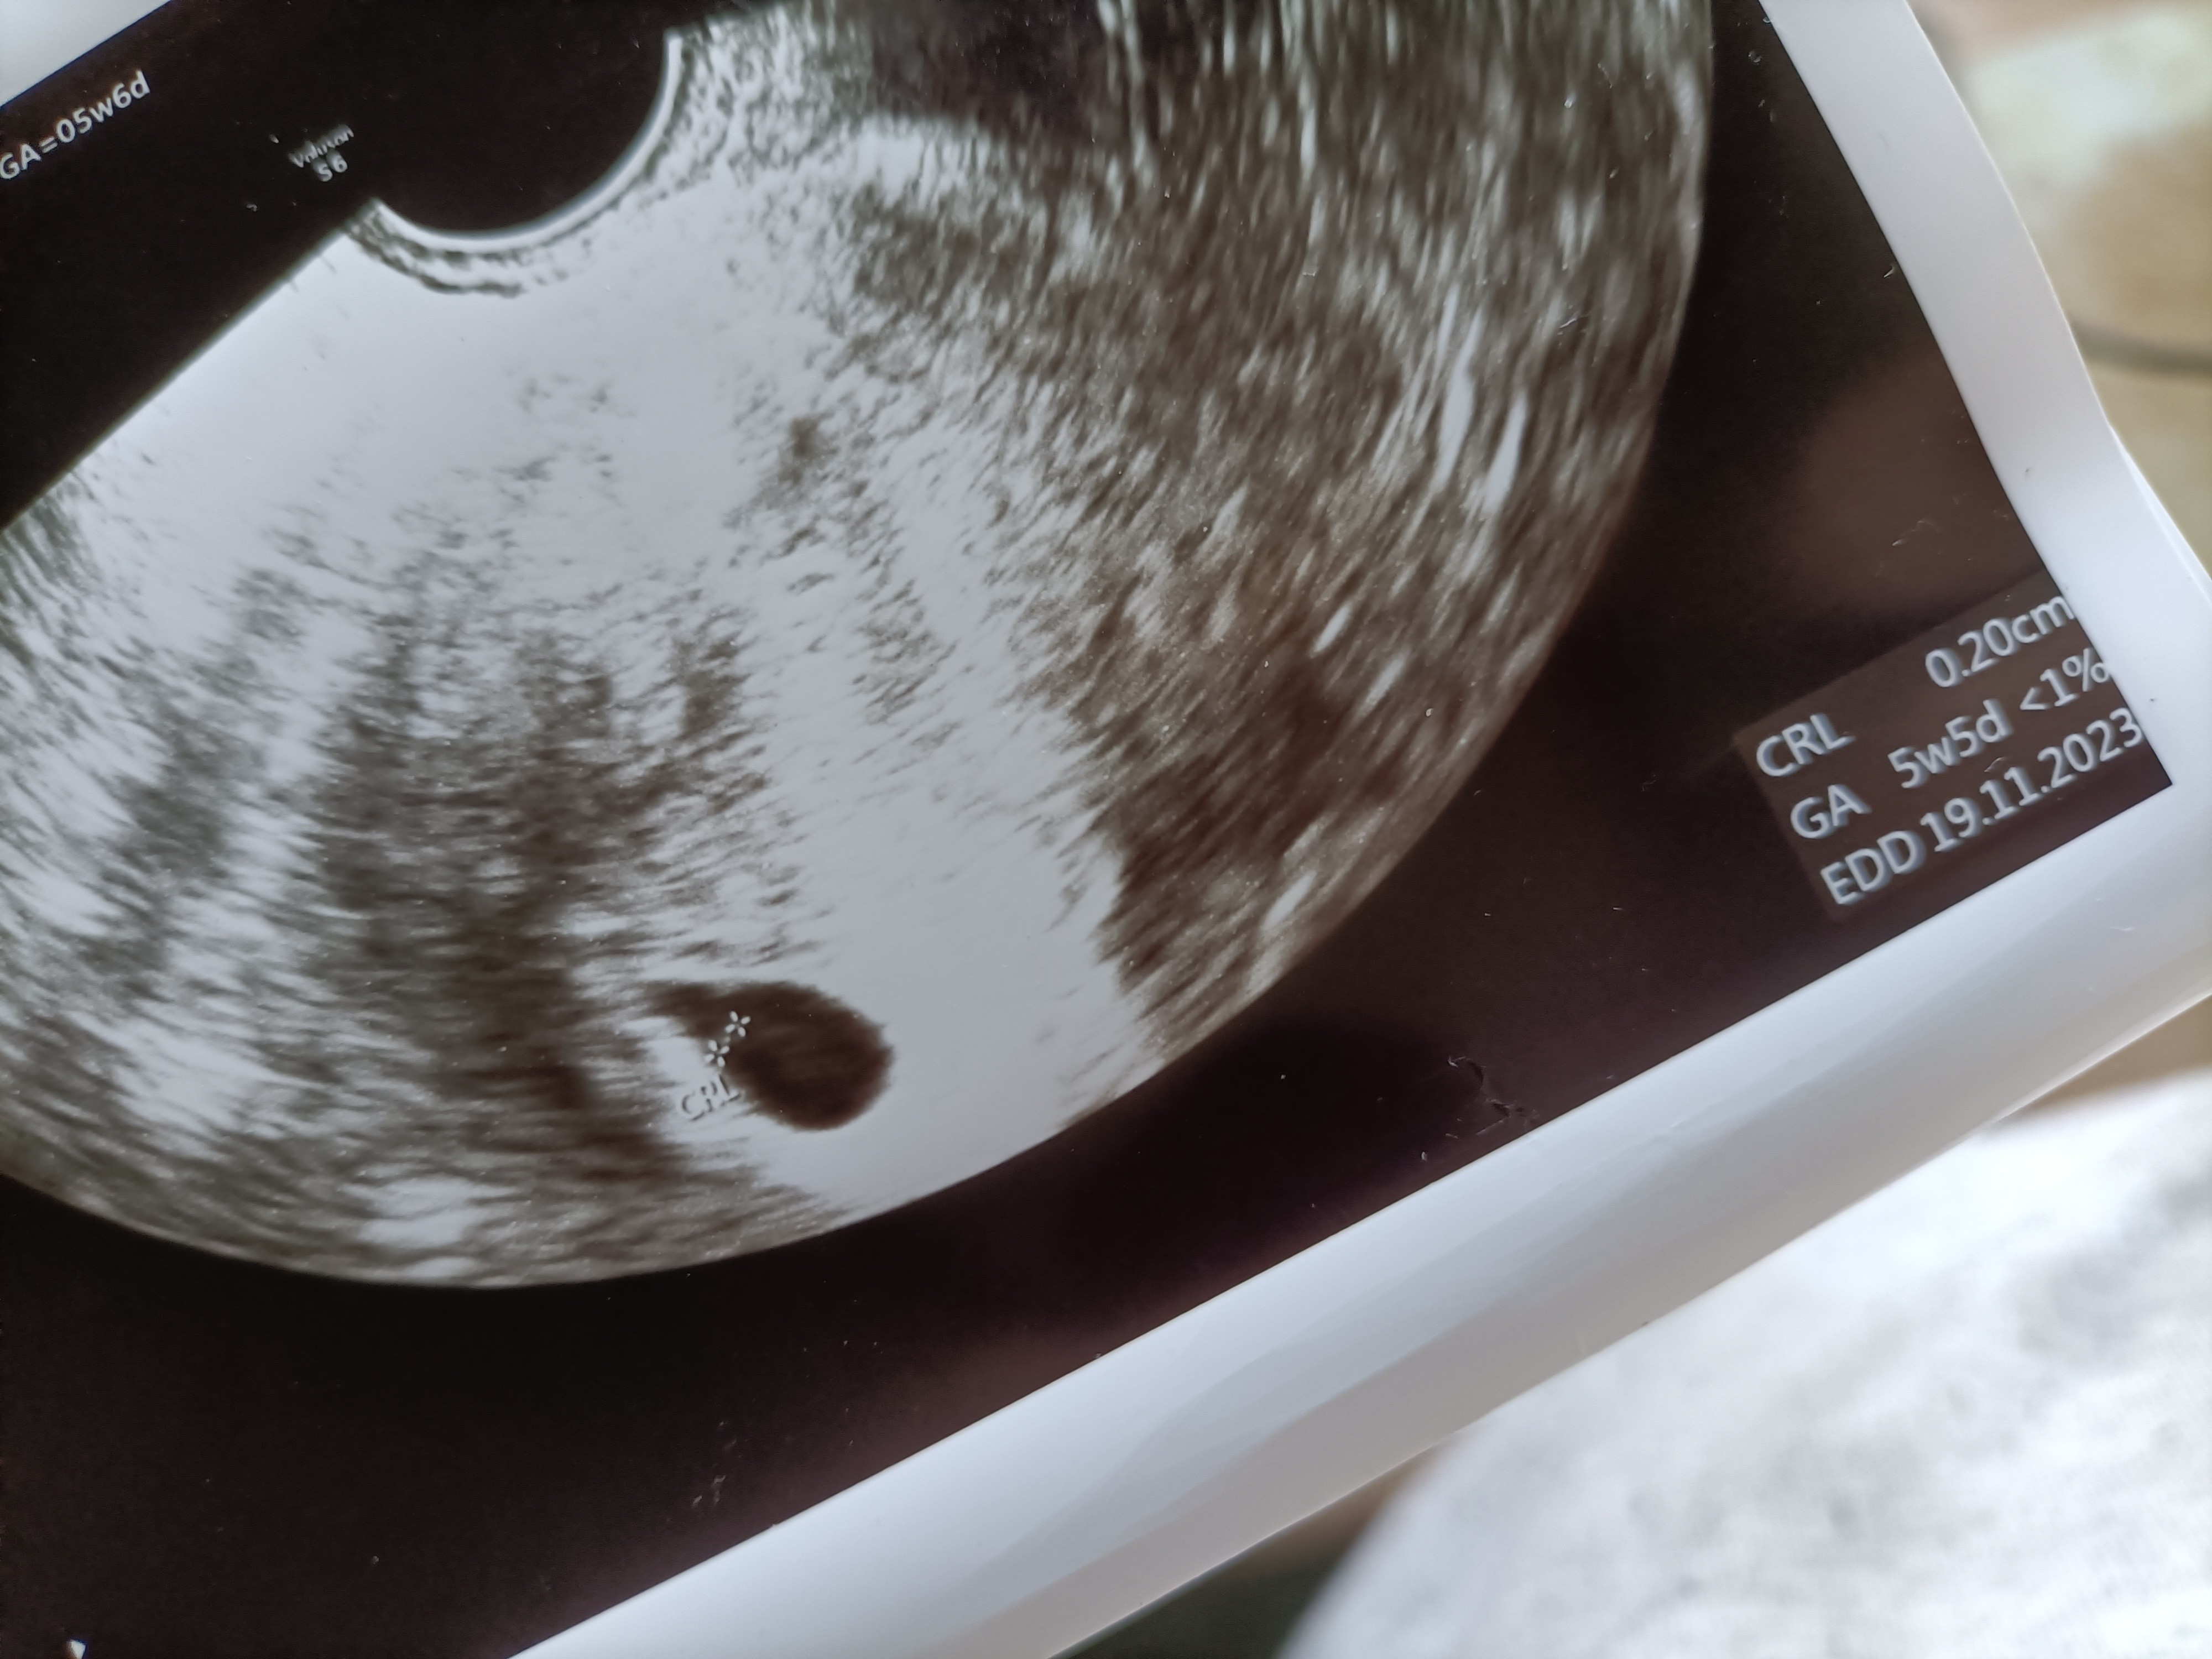

Pusty pęcherzyk

Witam, wiem że tematy były różne przekopałam internet wiem że są lekarze byłam u dwóch ale szukam pocieszenia informacji w czasie oczekiwania na nastepna wizytę. A więc zobaczyłam upragnione dwie kreski 9 dpo potwierdzonej testami owulacyjnymi, USG po owulacji zaraz że była i progesteronem. Termin z om 18 listopada na wizycie byłam 5+6 od razu na dwóch wizytach znaleziony pęcherzyk w jeden dzień 11mm ci pusty na drugim 15 mm po długich poszukiwaniach siusianiu między czasie żeby było lepiej widać. Czy jeśli owualcja się nie przesunęła, 28 od zagnieżdżenia jest szansa na rozwój czegokolwiek? Lekarz nie do końca ocenił co to za kropeczka cykle regularne 28 dni. Z córką na tym samym etapie 6+1 w tym samym dniu po owulacji podobny test i wynik bety a 6+1 był zarodek prawie 0.5 cm i bijące serduszko pozdrawiam

Ale czemu masz wątpliwości skoro jest pęcherzyk? Wg wyliczeń na USG masz termin na 19.11 i było wtedy 5tygodni i 5 dni z pomiarów. Przecież się mniej więcej zgadza. 😉

A czy nie powinno już być widać coś więcej niż tylko pęcherzyk ? Lekarz dodał żeby się rodzinie nie chwalić. Z córką ten sam etap i ten sam schemat testów potwierdzenia było już dużo widać razem z serduszkiem